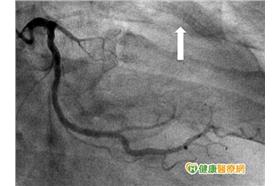

冠狀動脈阻塞 繞道手術解決心臟問題

74歲的賴先生,過去受到心臟病困擾,並於多年前因冠狀...